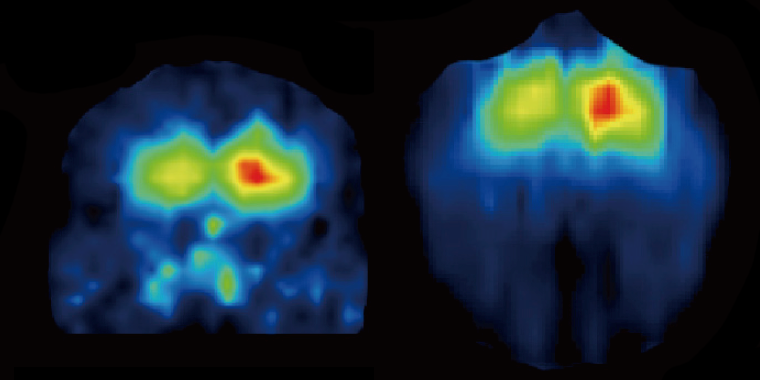

The researchers applied gene therapy for calbindin to one brain hemisphere in nine monkeys to compare the survival rates of dopamine neurons and preference for limbs between the two sides of the body.

Cells in the brain hemisphere that received the gene therapy showed a 50% higher survival rate than the other side, and the monkeys showed a preference for using limbs controlled by the treated hemisphere.

"Neurons positive for proteins that form plaques were more prevalent on the control hemisphere, indicating reduced pathology and reduced Parkinson's symptoms on the treated side of the brain." says Inoue.

MRI images of the coronal and axial planes of the brain. Note the differences in the treated side (right hemisphere) and untreated control side (left hemisphere) (Kyoto University / Takada Lab)